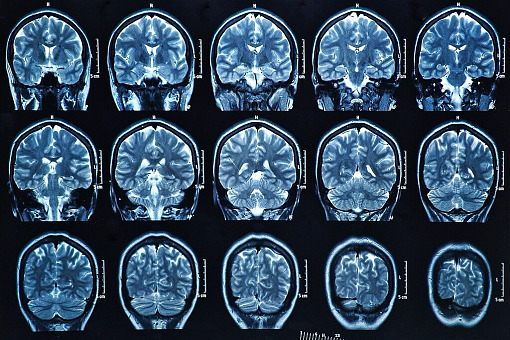

AI wykrywa brakujące zmiany w obrazach MRI

Według nowych badań moduł sztucznej inteligencji (AI) typu open source może pomóc w identyfikacji zmian padaczkowych na obrazach MRI, przeoczonych przez je analizujących, w tym ogniskowej dysplazji korowej (FCD) i stwardnienia hipokampa.

Do tej pory podejmowano różne wysiłki, aby wykorzystać zautomatyzowane uczenie maszynowe do identyfikacji FCD. Adler, student medycyny na University College London w Londynie wraz kolegami opracowali program uczenia maszynowego typu open source, opublikowany w 2022 r., który wykorzystuje sieć neuronową do wykrywania FCD na podstawie 33 cech powierzchniowych u 618 pacjentów z padaczką i 397 osób kontrolnych z 22 światowych ośrodków leczenia padaczki.

Ich zespół przeszkolił i dokonał walidacji krzyżowej sieci na połowie kohorty, a następnie przetestowali ją na drugiej połowie, w której miała ona czułość 59 proc. i swoistość 54 proc. Swoistość wzrosła do 67 proc. po uwzględnieniu granicy wokół zmian, która uwzględniała niepewność wokół granic ręcznie wyznaczonych masek zmian.

Stworzony algorytm bada każdy punkt powierzchni mózgu i decyduje czy przypomina on zmianę. Doprowadziło to do odkrycia zmian u 63 proc. pacjentów z ujemnym wynikiem MRI, ale doprowadziło również do znacznej liczby wyników fałszywie dodatnich, co zmusiło neurologów do wielu wysiłków, aby przejrzeć i potwierdzić takie wyniki, i okazało się, według Adlera, że jest to problem także w przypadku innych metod wykorzystujących AI.

Grupa opracowała również algorytm wykrywania stwardnienia hipokampa, które odpowiada za około 10 proc. zmian pomijanych przez MRI. Opiera się on na podobnym podejściu do cech powierzchniowych z podejściami normalizacyjnymi, a grupa pracuje obecnie nad włączeniem obu w jeden algorytm.